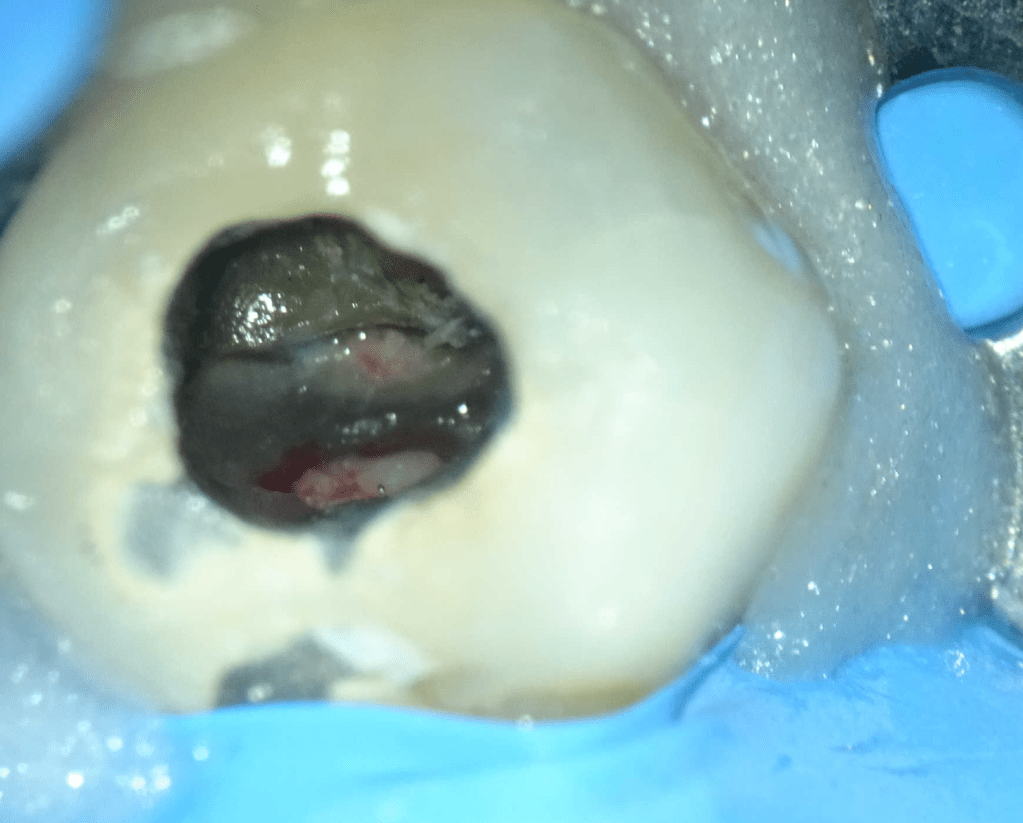

Reco pared vesticular

Reco pared vesticular